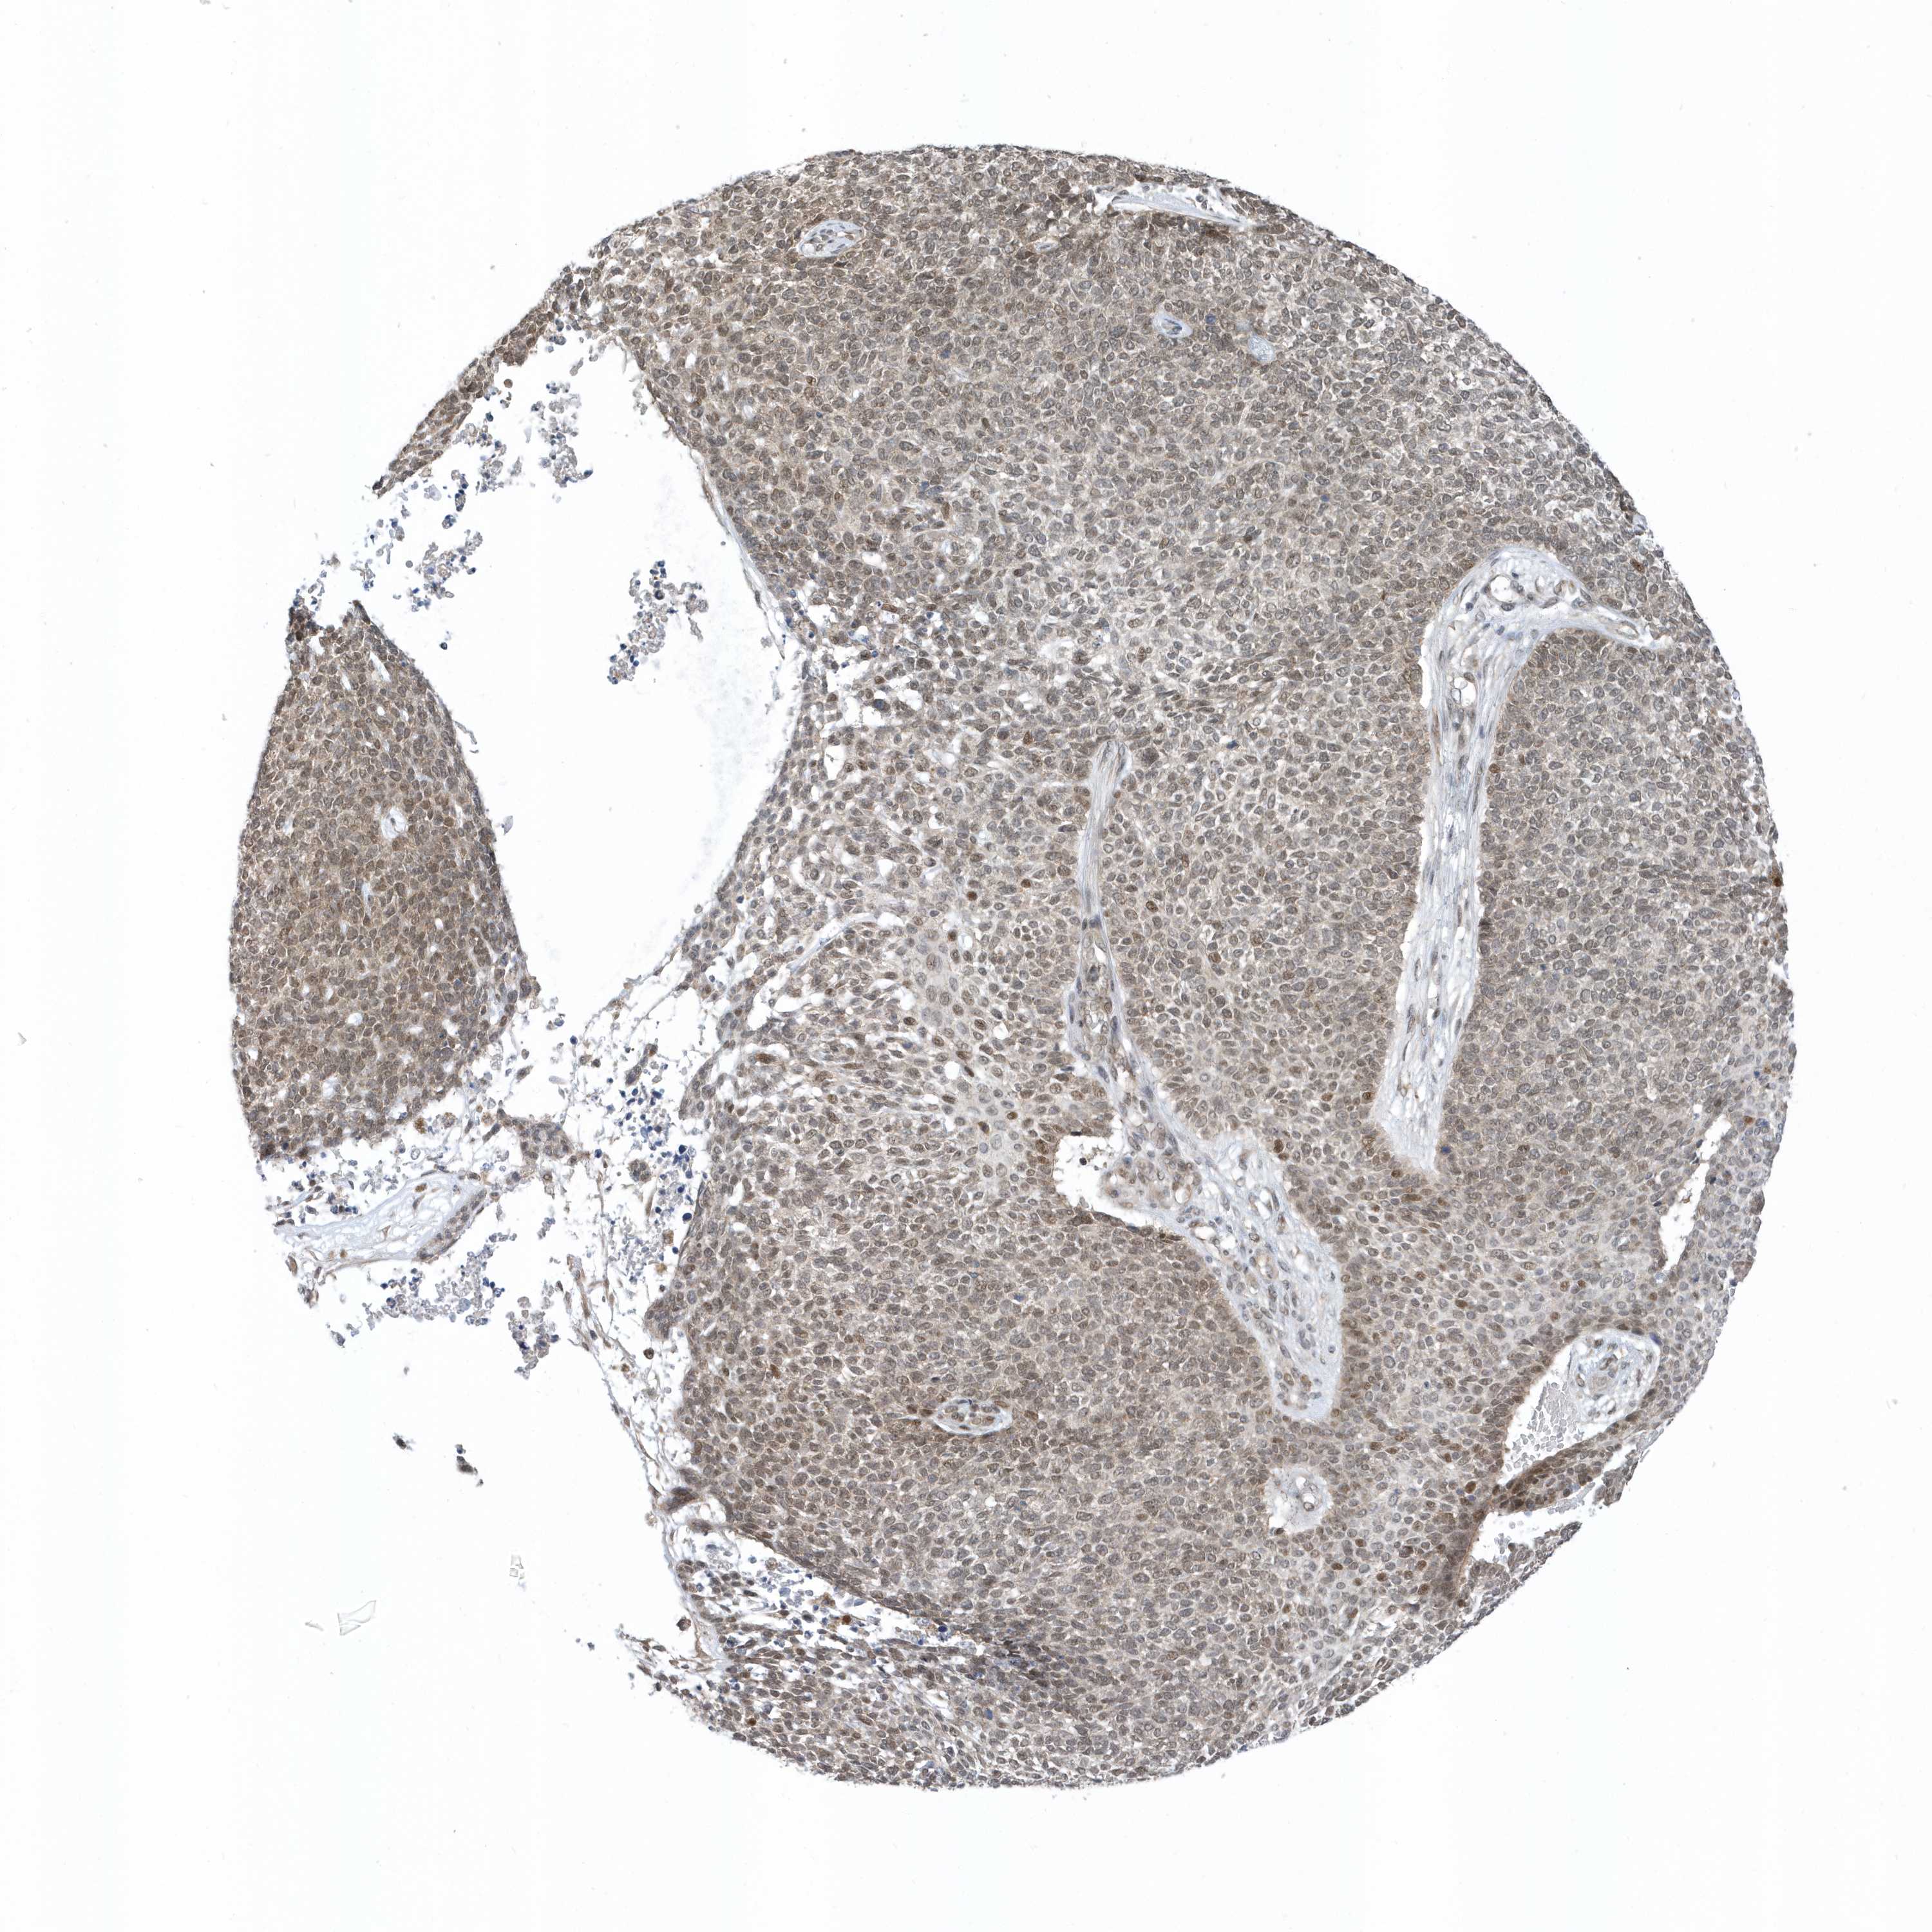

Basal cell and squamous cell cancer

SKIN CANCER - Protein expressioni

A mouse-over function shows sample information and annotation data. Click on an image to view it in a full screen mode. Samples can be filtered based on level of antibody staining by selecting one or several of the following categories: high, medium, low and not detected. The assay and annotation is described here.

Each image is clickable and will lead to virtual microscopy that enables deeper exploration of all samples and also displays staining intensity scores, fraction scores and subcellular localization as well as patient and tissue information for each sample.

Antibody HPA035844

Antibody HPA035845

Squamous cell carcinoma, NOS